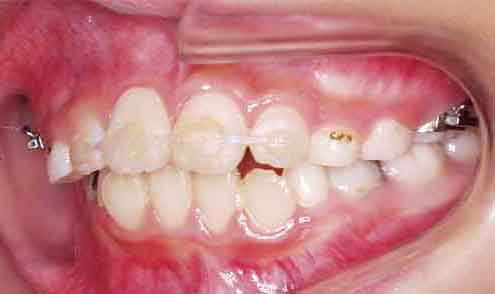

初診の状態